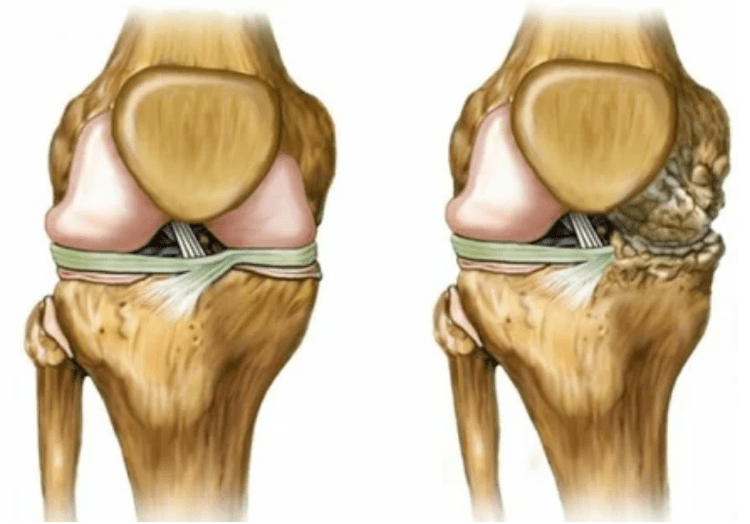

The last degree of the disease leads to:

- Involvement in the pathological process of bones, under and above cartilaginous surfaces;

- irritation of an joint shell, limiting mobility, which leads to a handicap of 2 degrees;

- increase in the density of the capsule;

- Reduce the gap in the gap of the joint, which becomes noticeable in the image.The stadium of violation is determined by the diagnosis-tantalist.The patient feels complexity or inability to straighten and completely fold the member;

- Joint deformation, cartilage acquires an irregular shape, causing a curvature;

- Deterioration of the patient's condition with complete destruction of the joint.